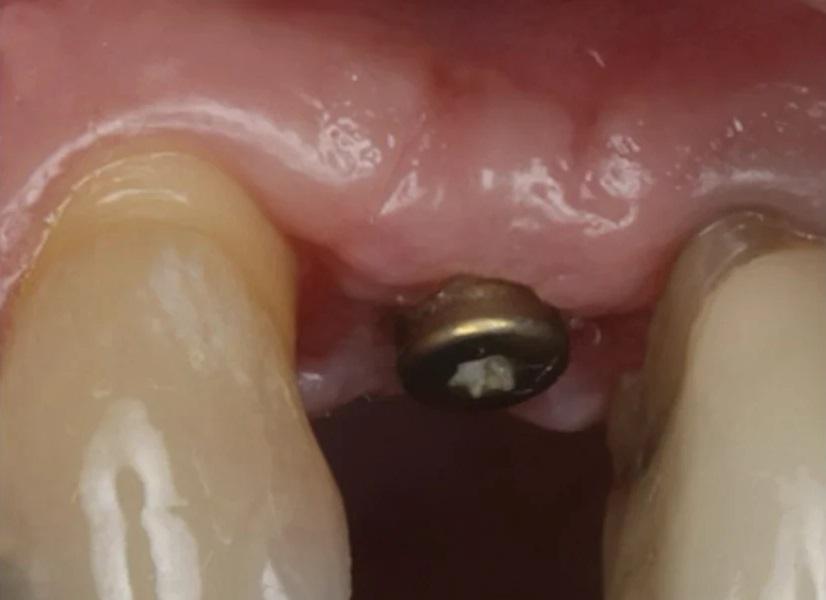

Раскрытие имплантата: Через шесть месяцев после установки имплантата были выполнены оценка мягких тканей и рентгенография (Фото 17). Была проведена местная инфильтрационная анестезия препаратом Septocaine, выполнен гребневой разрез для обнажения ранее установленного имплантата. Была установлена формировательная головка (Фото 18). ПА рентгеновский снимок подтвердил краевое прилегание абатмента к имплантату (Фото 19). Участок был ушит швом ПТФЭ, и пациенту были даны инструкции по гигиене полости рта и послеоперационному уходу. Контрольный осмотр проведен через 2 недели после раскрытия имплантата, мягкие ткани выглядели здоровыми (Фото 20 и Фото 21).

Фото 17. Окклюзионный вид здоровых мягких тканей и ширины гребня через 6 месяцев после установки имплантата.

Фото 18. Вестибулярный вид непосредственно после раскрытия имплантата, установки абатмента и коррекции вестибулярной мягкой ткани.